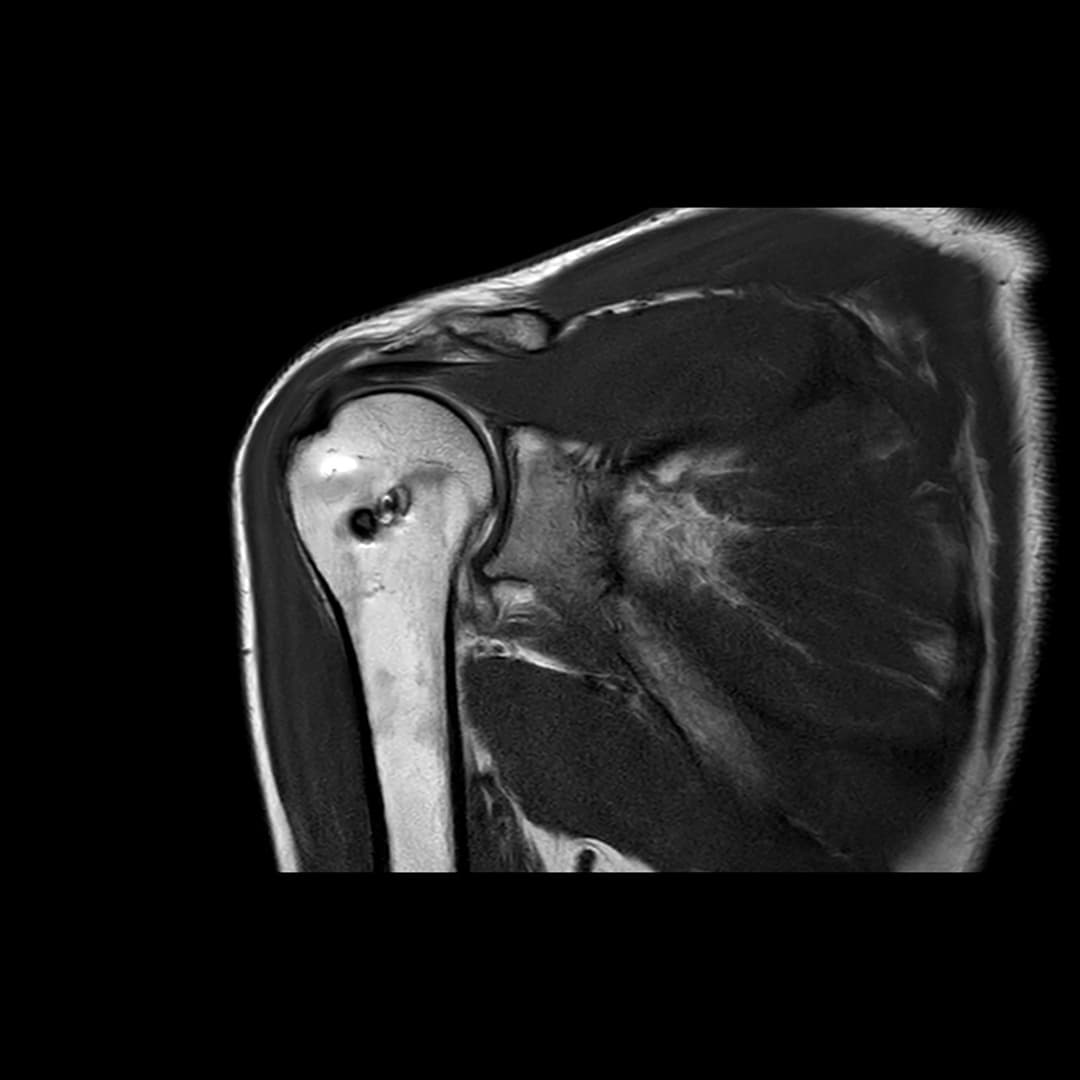

IRM

Ténodèse du long biceps intacte. Tendons sus et sous épineux respectés. Large diffusion du contraste depuis compartiment articulaire vers la BSAD.

Rupture du tendon sous-scapulaire avec rétraction grade II-III